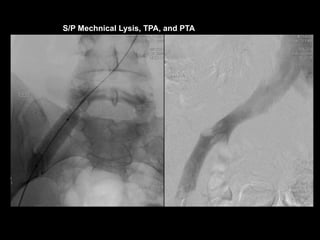

41 YO F, May - Thurner

Lack of Augmentation – suspect upstream obstruction

LCIV

External iliac vv.

S/P Mechnical Lysis, TPA, and PTA

Indirect Dx by arterial CTA

• 120 cc contrast

• Monitoring delay = 40sec

• Smart prep at infrarenal IVC

28F May-Thurner syndrome,

CIV/EIV stent placement

3 years ago

Courtesy of Anne Chin, MD